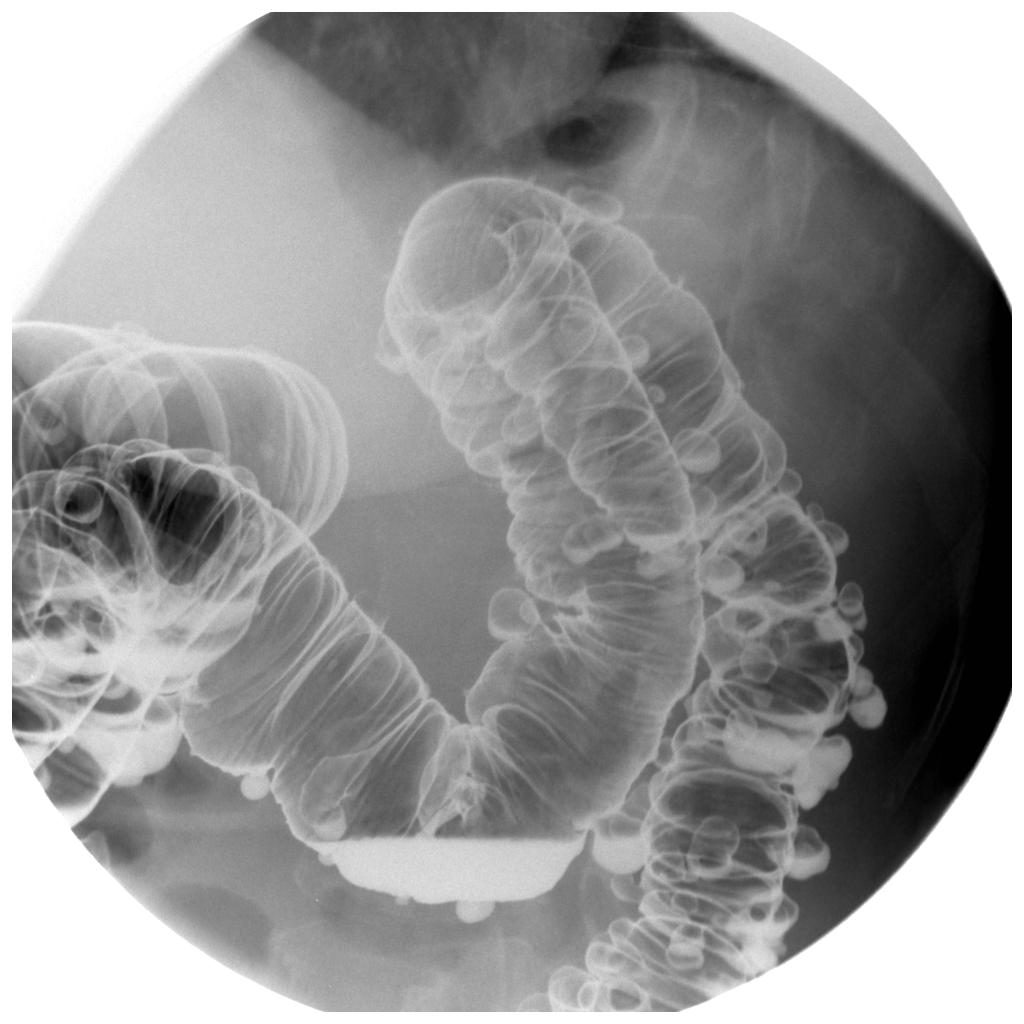

Рентгенография на корем (в изправено или легнало положение) показва наличието на въздух в коремната кухина, който се появява, ако има перфорация на чревната стена.

Колоноскопия се извършва, ако има кървене в съответния раздел на червата, както и за установяването/отхвърлянето на други възпалителни заболявания (напр. улцерозен колит), или ако се планира нехирургична процедура.